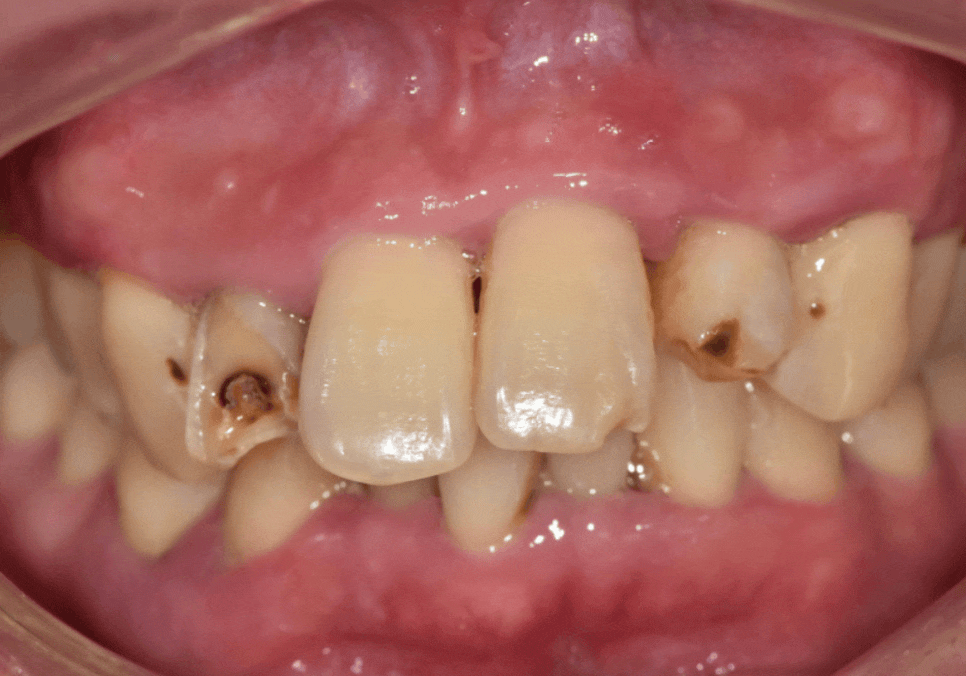

입안을 자세히 살펴보니

치료가 필요한 치아가 총 5군데였습니다.

앞니, 치아 상태

강동구 앞니 충치

치아 겉면에 충치가 살짝 진행된 상태

음식을 씹다 살짝 파절(깨짐)된 상태

충치 범위가 넓고 마모까지 심한 상태

이 중 가장 문제는

오른쪽 옆 앞니(#12)였습니다.